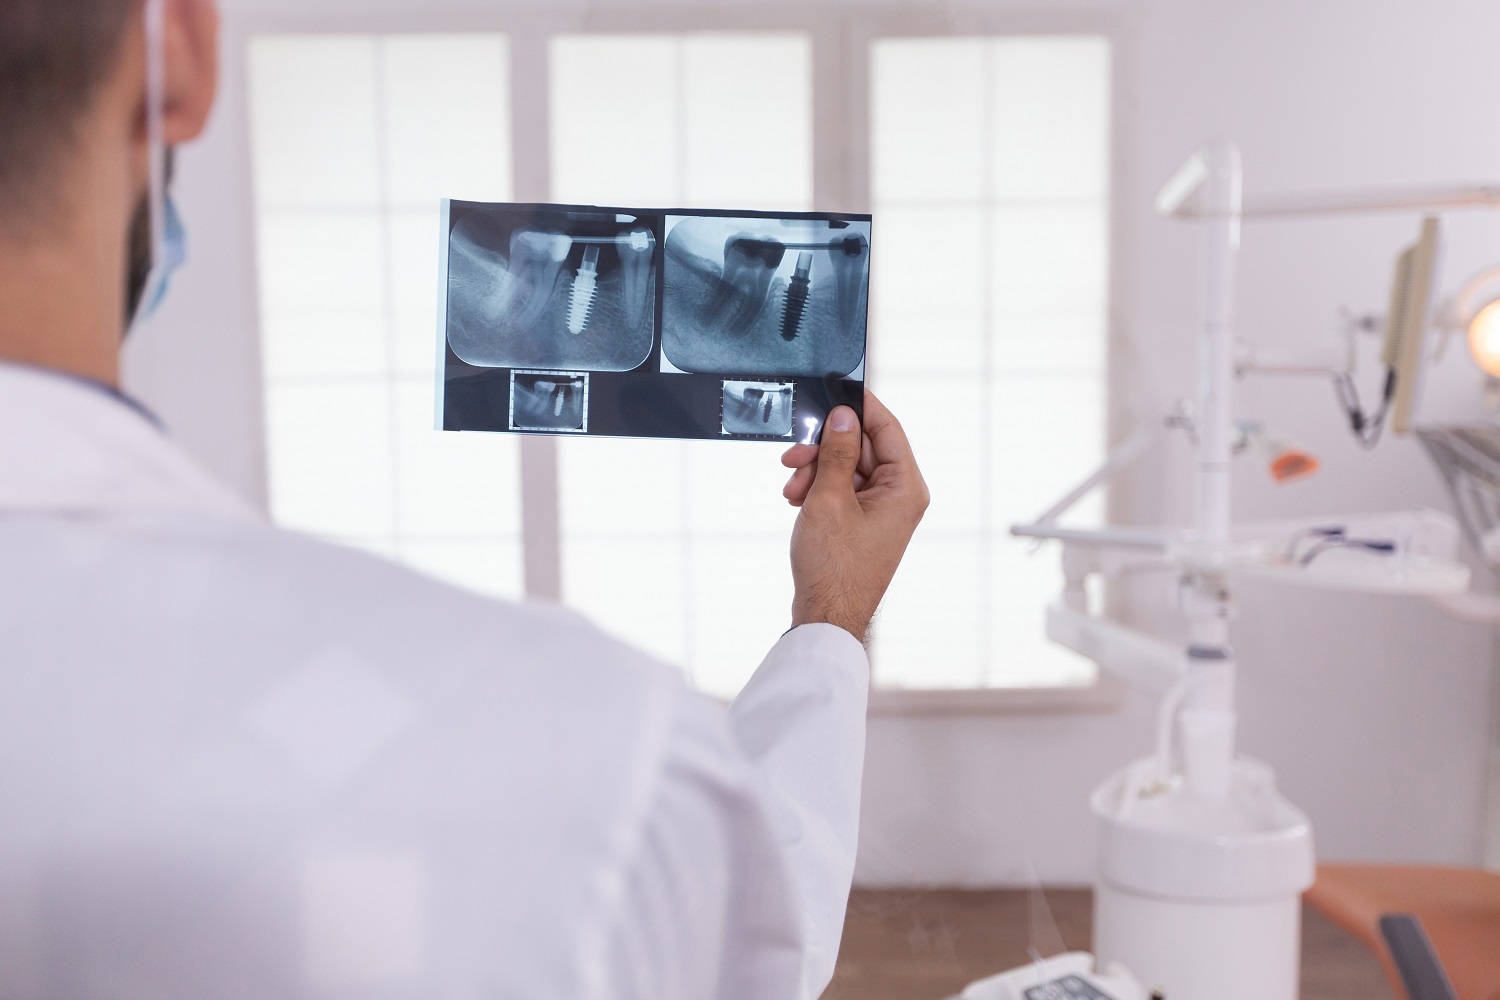

Ankara Üniversitesi Diş Hekimliği Fakültesini bitirdikten sonra aynı üniversitenin Ağız ,Diş ve Çene Cerrahisi Anabilim Dalı’nda doktora ve uzmanlık eğitimimizi tamamladık. 2007 yılında açtığımız kliniğimizde diş hekimliği genel tedavileri haricinde başlıca, çenelerdeki dişsiz boşlukların implant yerleştirilerek fonksiyon ve estetik görünümünün sağlanması , bu işlemi yaparken yetersiz kemik ve yumuşak dokuların arttırılması için hastanın kendinden alınan veya dışarıdan temin edilen kemik greftleri ile tedavi edilmesi, gömülü kalmış dişlerin ameliyat ile çıkartılması, çene kistleri ve tümörlerinin cerrahi tedavisi, çene eklemi ağrıları ve işlevsel bozukluklarının lazer tedavisi başta olmak üzere çeşitli tedavi yöntemleri ile giderilmesi, dil ve dudak sinirlerinin hasarına bağlı olarak gelişen uyuşukluğun ve iyileşmeyen ağız içi yaralarının düşük akım lazer metodu ile tedavi edilmesi, çenelerdeki gelişimsel bozuklukların ortognatik cerrahi ile estetik olarak düzeltme tedavileri verilmektedir.